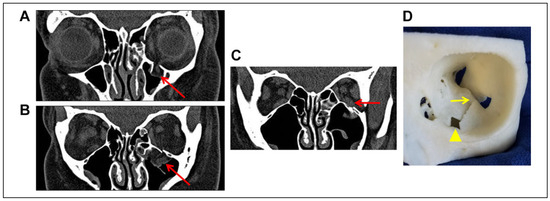

Introduction: Orbital floor fractures occur commonly as a result of blunt trauma to the face and periorbital region. Orbital floor fractures with a “trapdoor” component allow both herniation and incarceration of contents through a bone defect into the maxillary sinus as the bone [...] Read more.

Introduction: Orbital floor fractures occur commonly as a result of blunt trauma to the face and periorbital region. Orbital floor fractures with a “trapdoor” component allow both herniation and incarceration of contents through a bone defect into the maxillary sinus as the bone rebounds faster than the soft tissue, trapping muscle, fat, and fascia in the fracture site. In children, the fractured floor, which is often hinged on one side, tends to return toward its original anatomical position due to the incomplete nature of the fracture and elasticity of the bone. The entrapment of the inferior rectus muscle itself is considered a true surgical emergency—prolonged entrapment frequently leads to muscle ischemia and necrosis leading to permanent limitation of extraocular motility and difficult to correct diplopia. For this reason, prompt surgical intervention is recommended by most surgeons. In adults, true entrapment of the muscle itself is not as common because the orbital floor is not as elastic and fractures are more complete. Methods: We present an adult patient with an isolated orbital floor fracture with clinical and radiologic evidence of true entrapment of the inferior rectus muscle itself. Results: Despite the delayed surgical repair (4 days after the injury), the patient’s inferior rectus muscle function returned to near normal with mild upward gaze diplopia. Conclusions: Inferior rectus entrapment in adults may more likely be associated with immobilization of the muscle without total vascular compression/incarceration significant enough to lead to complete ischemic necrosis. Full article